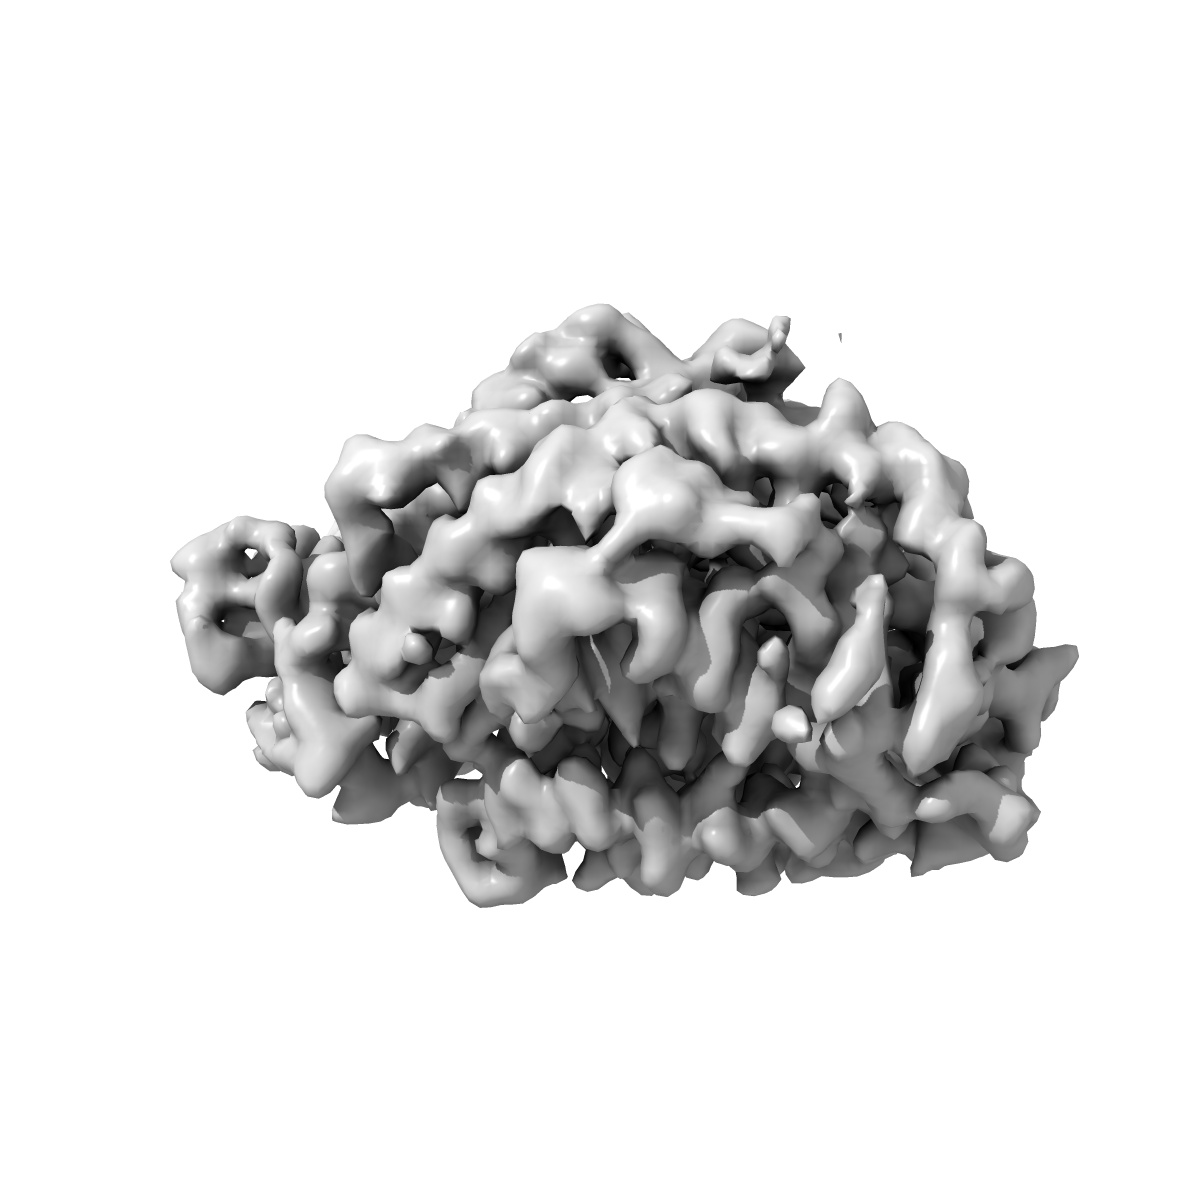

EMD-35626

SARS-CoV-2 XBB.1 spike glycoprotein in complex with ACE2 focused on RBD-ACE2 interface

Single-particle3.29 Å

Sample: SARS-COV-2 XBB spike glycoprotein in complex with ACE2

Fitted models: 8iov